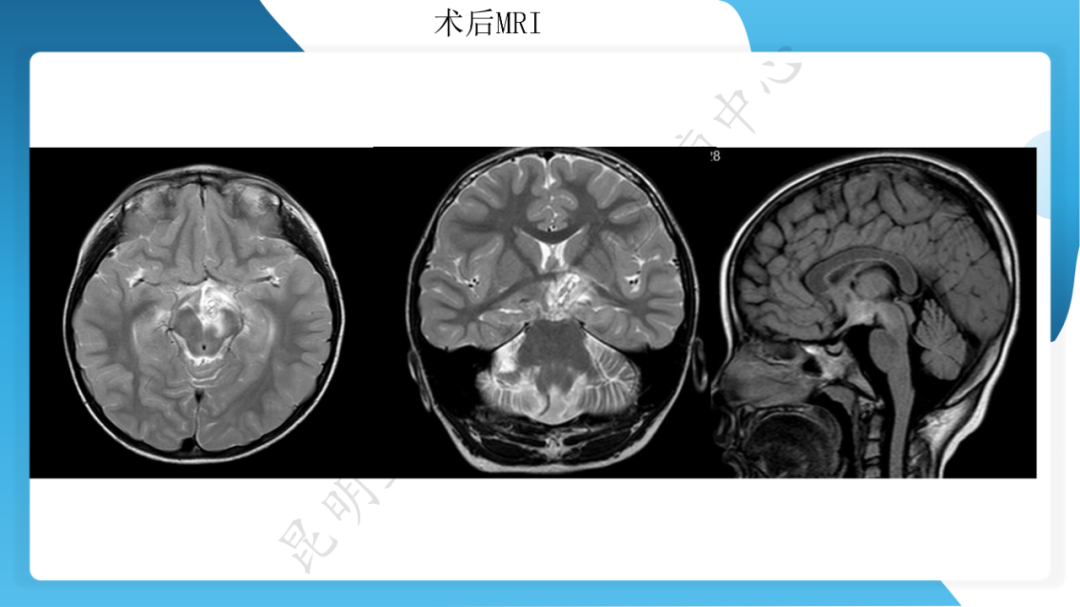

「痫停」信步》癫痫治疗病例荟萃第二十六期---SEEG 引导下射频热凝毁损治疗下丘脑错构瘤所致发笑癫痫